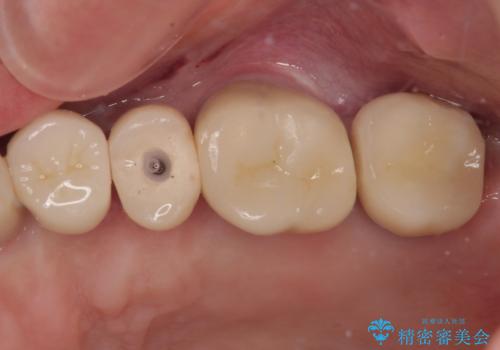

- 奥歯に装着していたクラウンが外れてしまったとのことで来院された患者様です。

診察したところ、歯根に破折線が確認され抜歯が必要な状態でした。

歯肉や歯槽骨の状態は良好であったため、抜歯即時埋入インプラントによる補綴治療を行うこととしました。